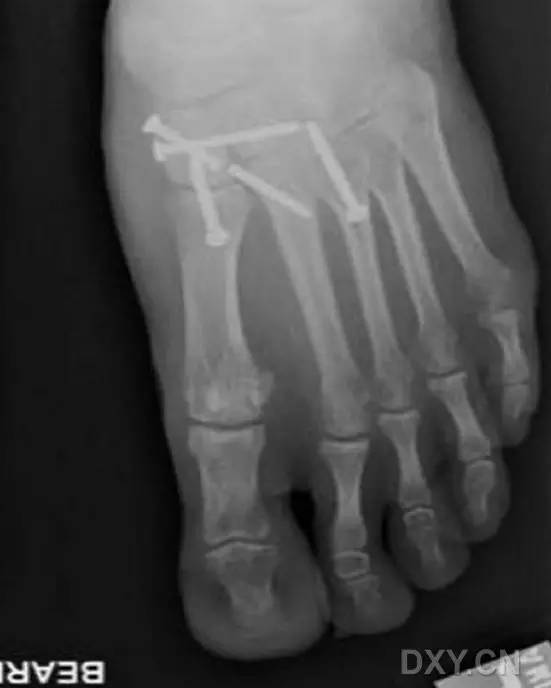

然而这种固定方式存在一大缺陷,那就是,一旦出现螺钉的断裂,将导致螺钉头端取出困难(图 2)。

图 2. 传统 Lisfranc 螺钉置入后,螺钉断裂,位于第 2 跖骨基底的螺钉尖端难以取出